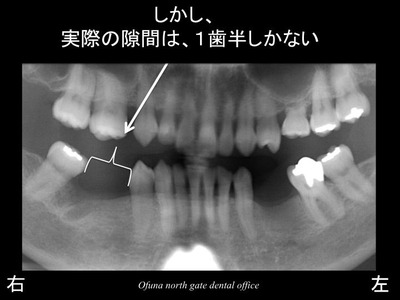

しかし、欠損部は2歯欠損のスペースはありません。

1歯と半分程度の隙間です。